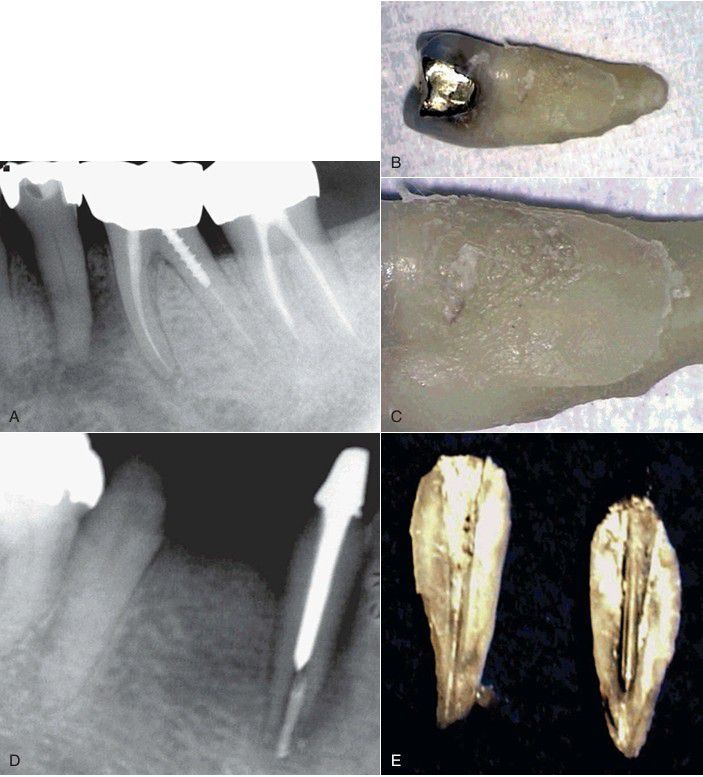

Poorly fitting intracoronal restorations can place stresses within the tooth that can cause a vertical root fracture. A, This radiograph of a mandibular second premolar (with a gold inlay) reveals extensive periapical and periradicular bone loss, especially on the distal aspect. B, The tooth pulp tested nonvital, and there was an associated 12-mm-deep, narrow, isolated periodontal pocket on the buccal aspect of the tooth. After the tooth was extracted, the distal aspect was examined. C, On magnification (×16) the distal aspect of the root revealed an oblique vertical root fracture. Similarly, the placement of an ill-fitting post may exert intraradicular stresses on a root that can cause a fracture to occur vertically. D, This radiograph depicts a symmetrical space between the obturation and the canal wall, suggesting a vertical root fracture. E, After the tooth is extracted, the root fracture can be easily observed.